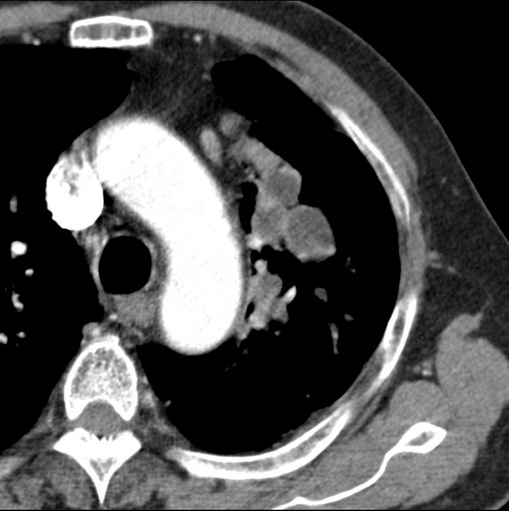

男性患者 81岁 咳嗽 咳痰 咯血

肿块贴近左肺门,包绕左上肺动脉,形态不规则。肿块增强扫描中度强化。纵膈内主动脉弓左旁间隙、气管隆突前、下间隙见多枚淋巴结影。综上考虑左侧中央型肺癌可能性大。图片没有完整上传,尤其是左肺上叶支气管分支层面没有上传,因此不好判断是叶支气管中断还是段支气管中断。另外,下图红色部分所示是“黏液支气管征”吗?